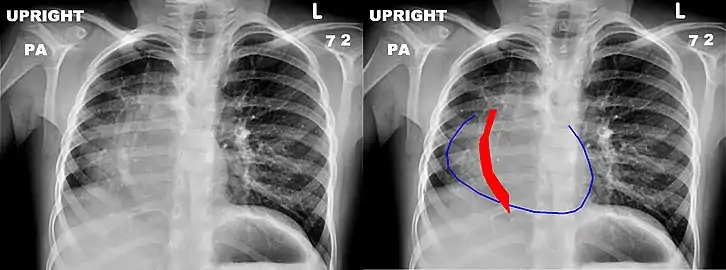

The anomalous venous return forms a curved shadow on chest x-ray such that it resembles a scimitar. This is called the Scimitar Sign. Associated abnormalities include right lung hypoplasia with associated dextroposition of the heart, pulmonary artery hypoplasia and pulmonary sequestration. Incidence is around 1 per 100,000 births.[4]

Chest x-ray of a five-year-old girl with Scimitar syndrome. The heart (blue outline) is shifted into the right half of the chest, and the anomalous pulmonary venous return (red) has a shape reminiscent of a Scimitar.